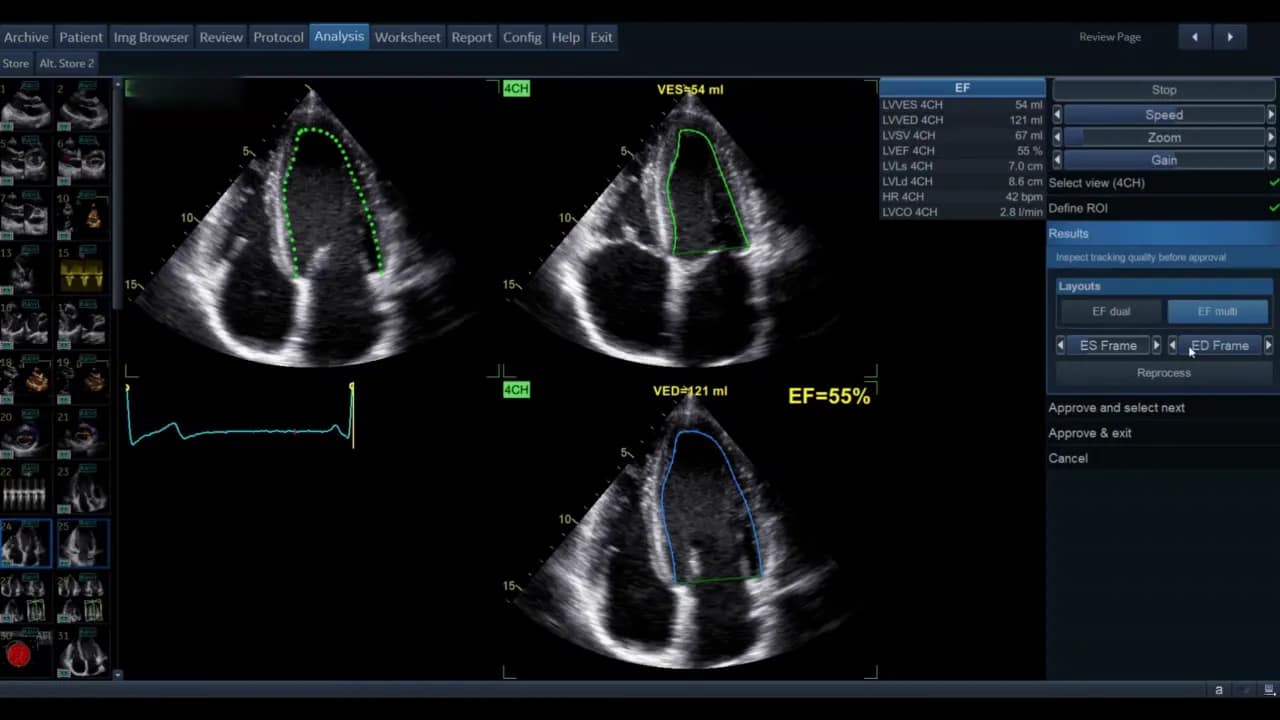

Die Ansicht kann als Einzelbild oder als EF‑Dual‑Display gezeigt werden. Im Dual‑Display sehen Sie gleichzeitig Systole und Diastole mit den berechneten Volumina und der Ejektionsfraktion als Prozentsatz.

Wenn die automatisch gewählten End‑Frames nicht korrekt sind, können Sie diese manuell auf der rechten Seite des Menüs ändern. Ebenso lassen sich Konturmarkierungen sowohl für systolische als auch diastolische Frames verschieben.

Wichtig: Jede manuelle Anpassung nach der initialen Prozessierung markiert das Ergebnis mit einem Sternchen. Dieses Sternchen signalisiert, dass Werte nachbearbeitet wurden. Wenn Sie Änderungen vor der endgültigen Auswertung sauber integrieren möchten, verwenden Sie die Reprocess Funktion, die eine erneute automatische Verfolgung nach Anpassung durchführt. So wird das Sternchen vermieden und die Konturoptimierung wird in den Algorithmus übernommen.

Die Software zeigt nach erfolgreichem Durchlauf die systolischen und diastolischen Volumina beider Ansichten sowie die berechnete biplane Ejektionsfraktion. Diese Werte erscheinen in der Ergebnisliste; die biplane EF wird in der Regel als kombinierter Wert ausgewiesen.

Wenn Sie zufrieden sind, wählen Sie Approve and Exit. Die Messwerte werden in das Arbeitsblatt bzw. in die Messliste übernommen. Wollen Sie die Ergebnisse verwerfen, wählen Sie Cancel.